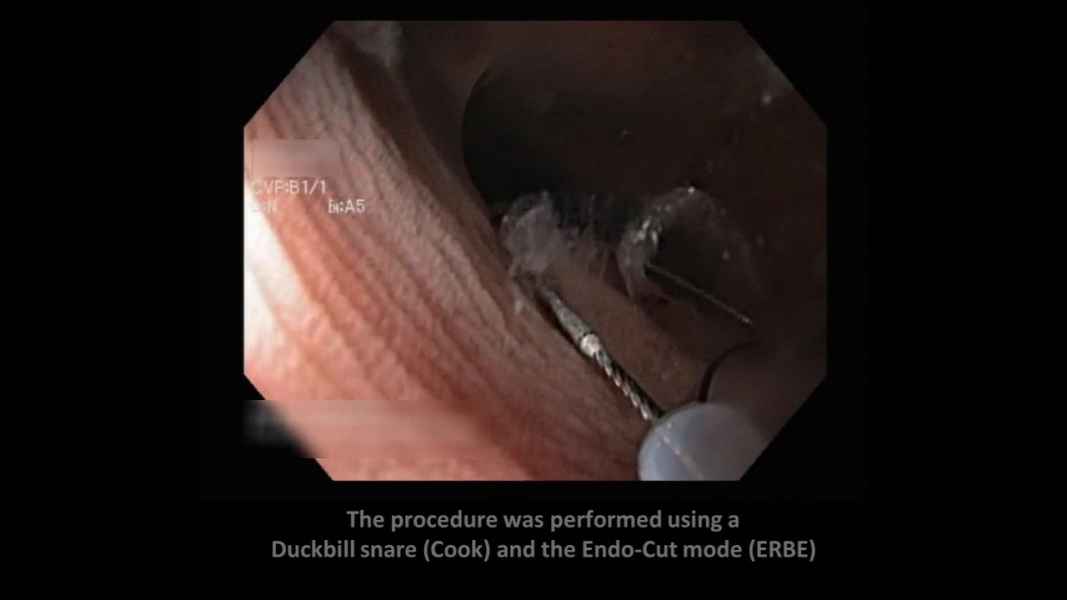

Estenose de Anastomose Hepatico-jejunal com litíase intra-hepática – Tratamento por CPRE com Enteroscópio

Fotografia